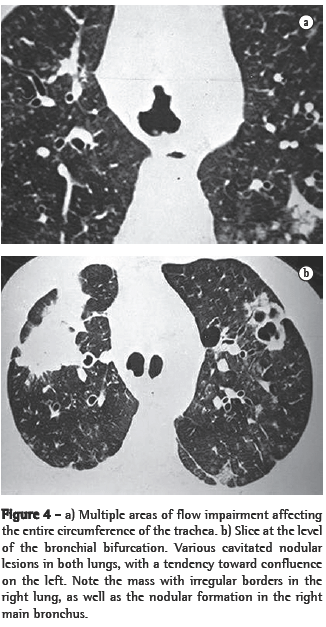

In all eight cases, the CT scans revealed polypoid formations in the trachea. In one case, injury to one of the main bronchi was identified. Seven patients presented involvement of the pulmonary parenchyma. In all eight cases, there were cavitated polypoid lesions, with irregular internal borders and walls of various thicknesses, multilobulated in six cases and presenting confluence of the lesions in five (Figures 1 through 5). Solid nodules were seen in six patients. An air-fluid level was observed in only one patient. The lesions were predominantly in the lung bases in three patients and in the middle thirds in two, whereas they were evenly distributed in two. In one patient, the lesions were accompanied by a mass, and, in another patient, they were accompanied by consolidation. In the latter case (Figure 5), there was malignant degeneration in multiple lesions. Signs of air trapping were also observed in one case. There were no identified instances of lymph node enlargement or pleural effusion.

Chest X-rays are inferior to CT scans of the chest, especially those performed using spiral CT (volumetric acquisition), in the initial phases of pulmonary dissemination, due to the fact that CT better characterizes and allows better visualization of nodular tracheobronchial vegetation, Tomographic findings include focal or diffuse airway narrowing caused by the nodules. The nodules form on the mucosal surface, and their invasion into the lumen is best evaluated using CT.(3) These alterations are easily correlated with the disease when there is a clinical history of papillomatosis.(4) Other findings related to airway obstruction and accompanying infections are atelectasis, consolidations, air trapping and bronchiectasis.(2-4) In our sample, polypoid formations in the trachea were observed on all of the CT scans Seven patients presented involvement of the pulmonary parenchyma, characterized by cavitated polypoid lesions with irregular internal borders and walls of various thicknesses, with a multilobulated aspect and a tendency toward confluence. Solid nodules were seen in six patients. None of the patients presented lymph node enlargement or pleural effusion.